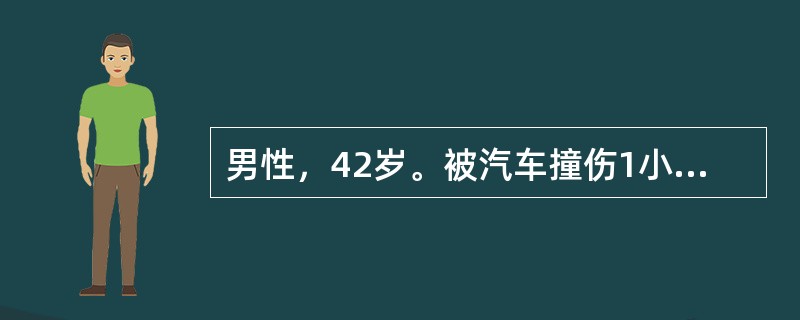

男性,42岁。被汽车撞伤1小时,昏迷状态。急诊CT检查图像如图所示.诊断最可能是()

A . 脑实质出血

B . 脑挫裂伤

C . 硬膜下血肿

D . 硬膜外血肿

E . 蛛网膜下隙出血

男性,42岁。被汽车撞伤1小时,昏迷状态。急诊CT检查图像如图所示.诊断最可能是<img border="0" style="width: 276px; heigh

[单选题]男性,42岁。被汽车撞伤1小时,昏迷状态。急诊CT检查图像如图所示.诊断最可能是A.脑实质出血B.脑挫裂伤C.硬膜下血肿D.硬膜外血肿E.蛛网膜下隙出